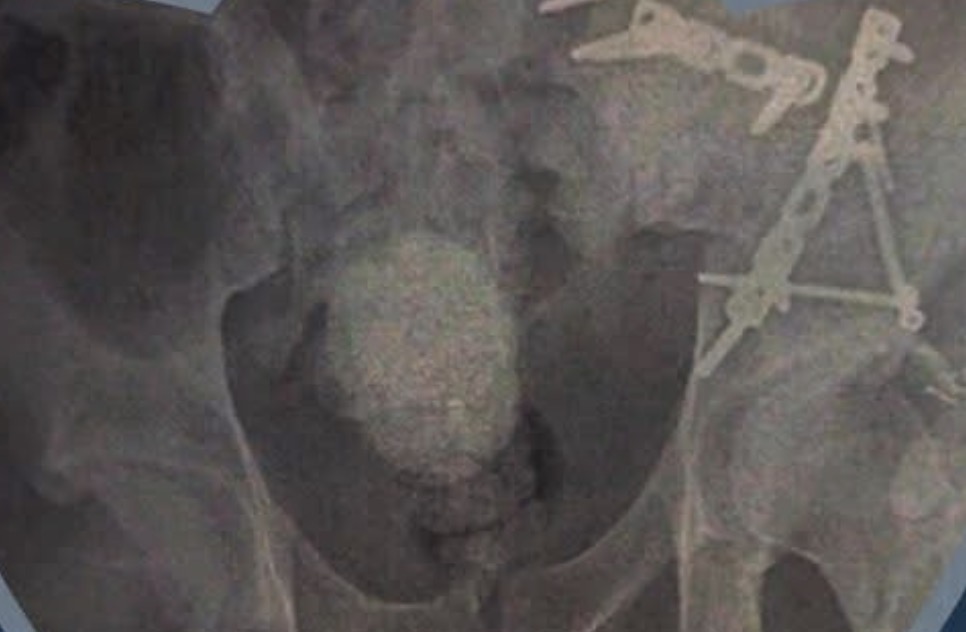

واستقبل المجمع حالة طبية حرجة تعاني من كسر معقد في عظام الحوض، مصحوبًا بكسر آخر في المفصل العجزي الحرقفي، وهي من الإصابات التي تتطلب دقة متناهية في التشخيص والتدخل الجراحي نظرًا لحساسية الموقع وقربه من الأعصاب والأوعية الدموية الرئيسية.

ونجح الفريق الطبي المتميز بقسم جراحة العظام في إجراء الجراحة بنجاح باهر، حيث تم رد الكسور وتثبيتها باستخدام تقنيات متطورة تضمن أعلى معايير الجودة والأمان.